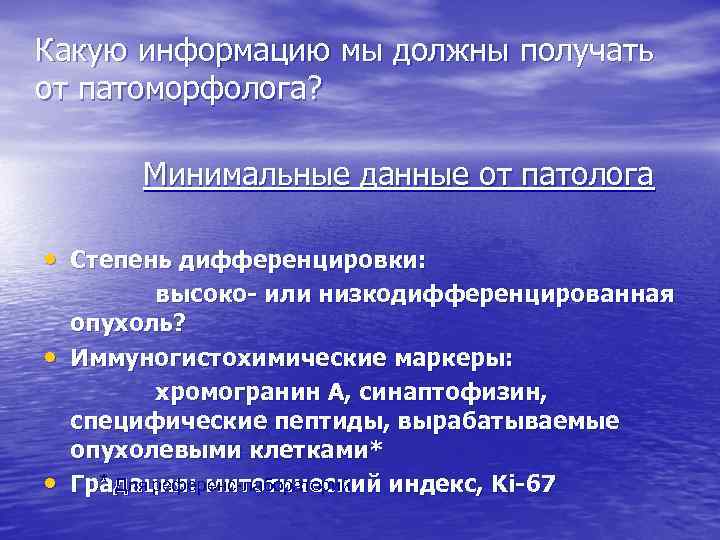

Какую информацию мы должны получать от патоморфолога? Минимальные данные от патолога • Степень дифференцировки: • • высоко- или низкодифференцированная опухоль? Иммуногистохимические маркеры: хромогранин А, синаптофизин, специфические пептиды, вырабатываемые опухолевыми клетками* * Для референс-лабораторий Градация: митотический индекс, Ki-67